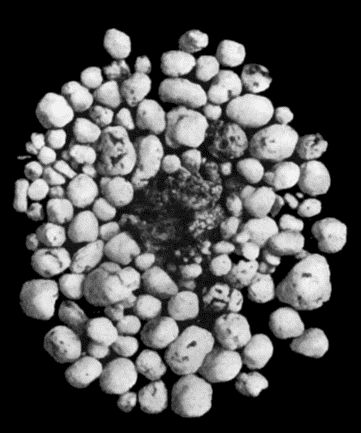

167.Loose Body from Knee-joint 541

168.Multiple partially ossified Chondromas of Synovial Membrane from Shoulder-joint 542

169.Multiple Cartilaginous Loose Bodies from Knee-joint 543